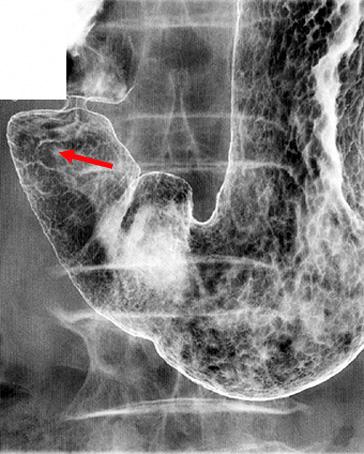

Criteria of Hist.ClassificationMalignant epithelial tumor/Adenocarcinoma

LocationStomach/Antrum

Technique, MethodX-ray

Macroscopic TypesType 0/IIc (IIc) Superficial depressed type

Size1 - 9

Depth of Tumor Invasionmucosa